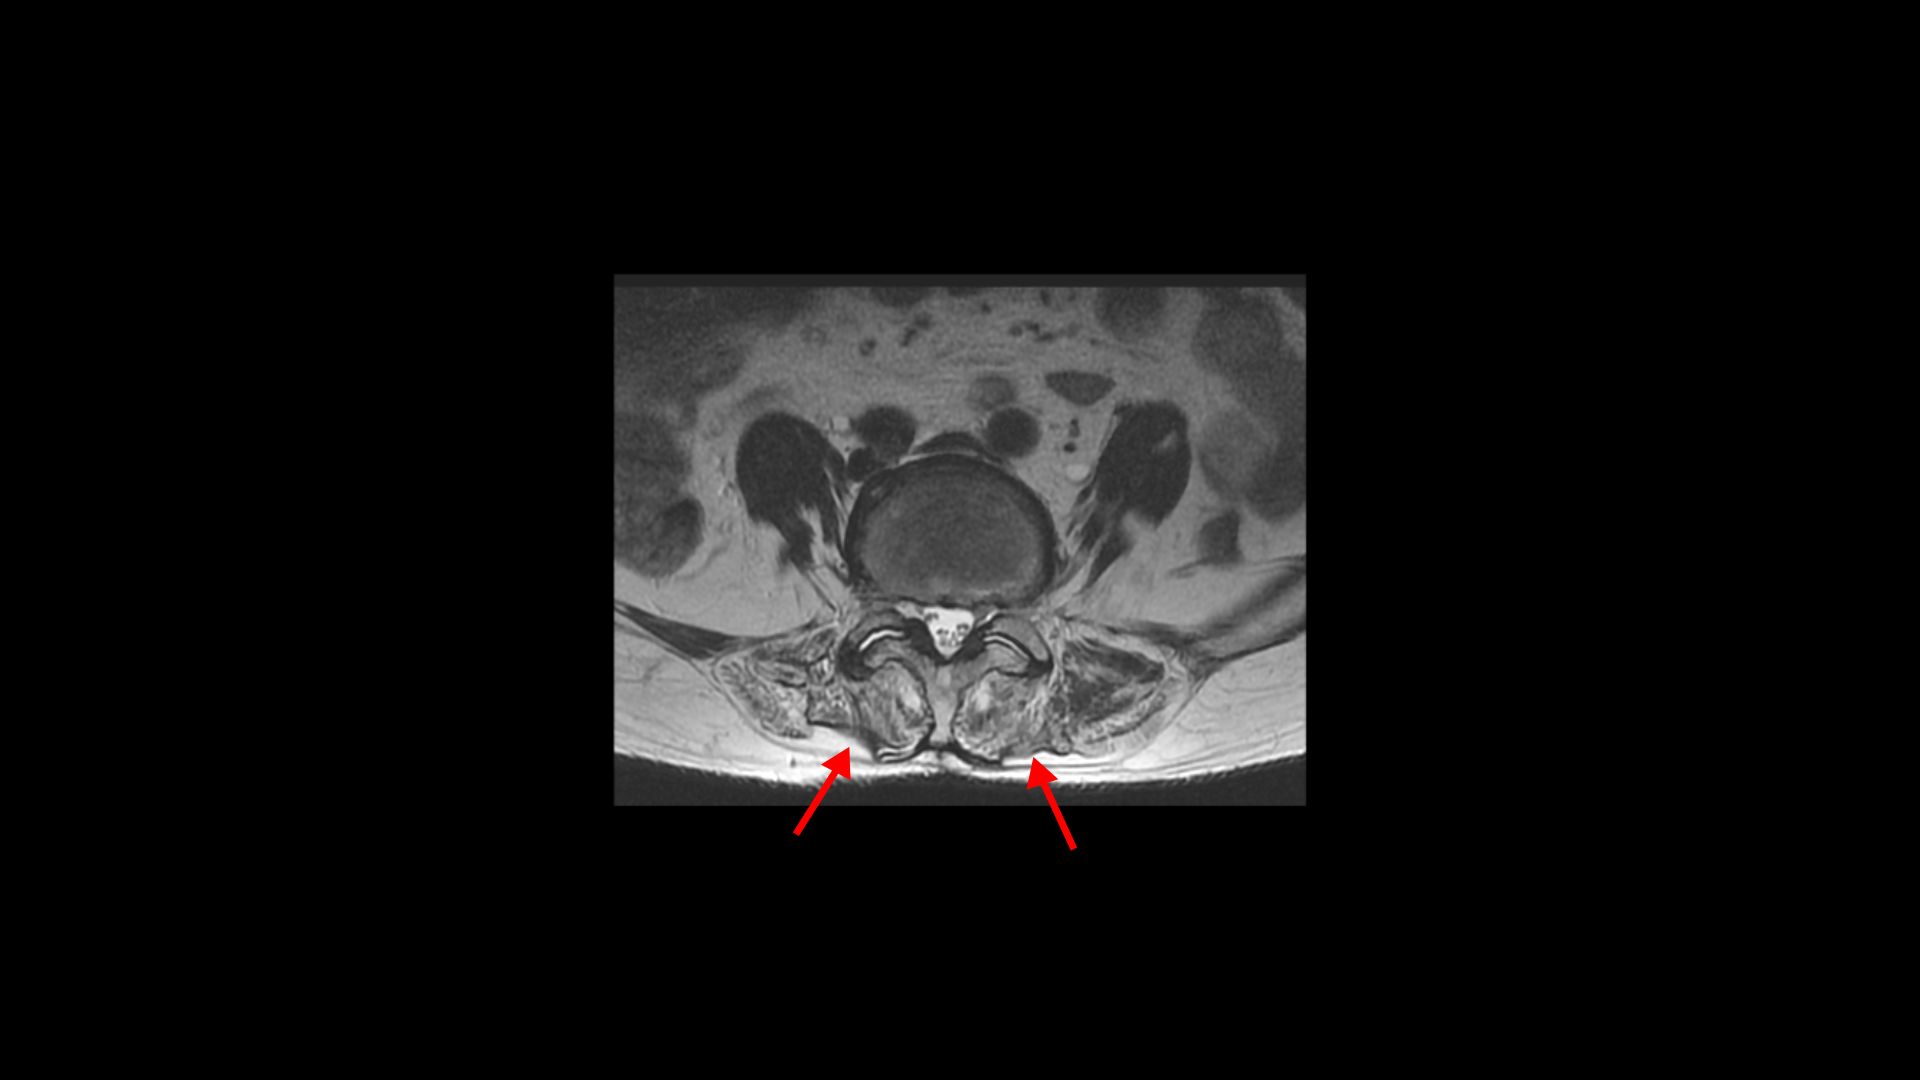

이분 MRI를 보면 74세의 연세답게 여러 마디의 퇴행성 디스크가 있습니다. 하지만 심하지 않습니다.

3번 4번에 황색 인대가 조금 두꺼워진 중심성 협착이 보이지만 역시 심하지는 않습니다.

좌우의 신경구멍도 막힌 곳이 없습니다.

이 환자분의 일어서면 허리가 구부러지고 다리가 아파 걷기 어려운 이유는 근감소증 때문입니다. 특히 근육 중에서도 MRI에서 보면 허리 뒷부분에서 허리를 펴주는 근육인 기립근이 보시다시피 하얗게 지방으로 변해있습니다.

이분하고 증상이 비슷한 다른 근감소증 환자분의 기립근도 마찬가지입니다.